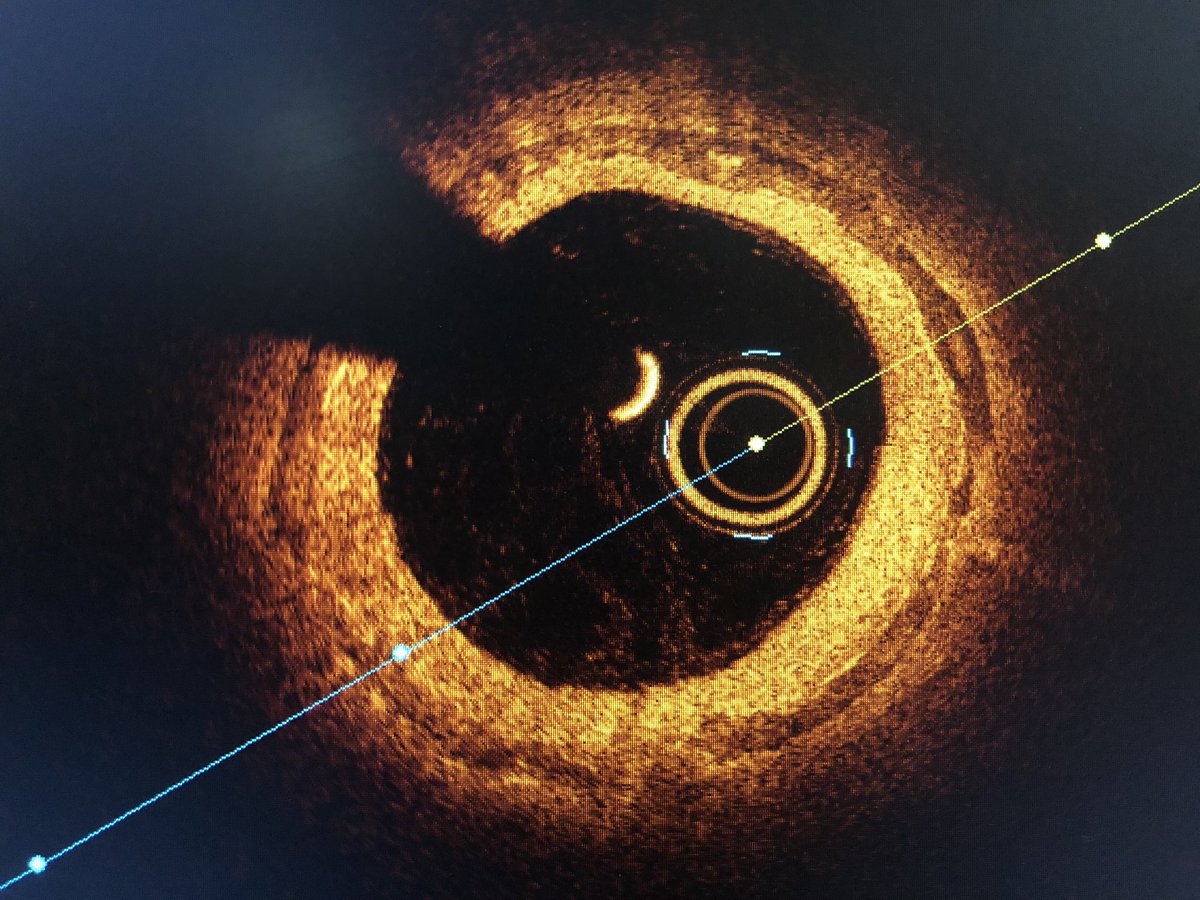

Vessel size and extent of calcium in tibial arteries frequently misjudged. #OCT of the left PTA reveals extensive medial calcification and MLD by EEL 3.5-4.0mm. Treated w/ OA and PTA w/ 4mm balloon for wound healing w/ good result #imagefirst #SCAIPAD